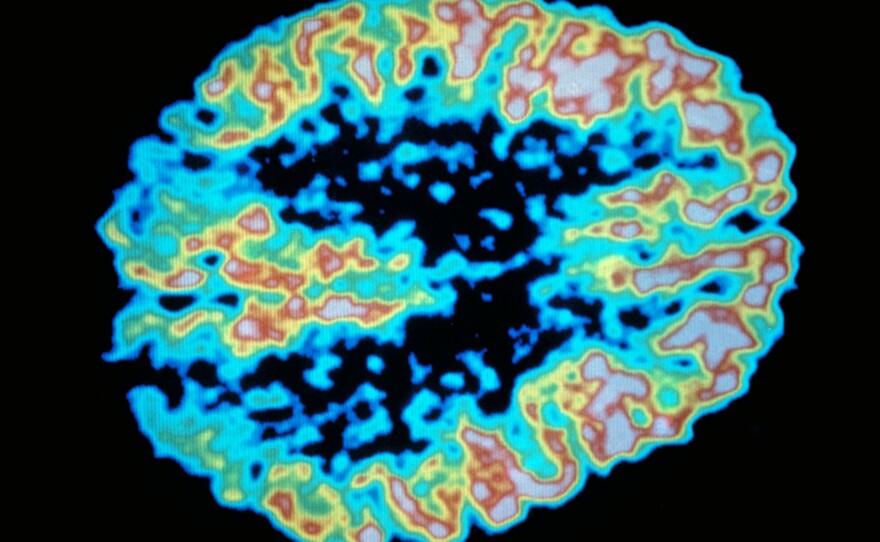

A PET scan shows metabolism of sugar in the human brain.